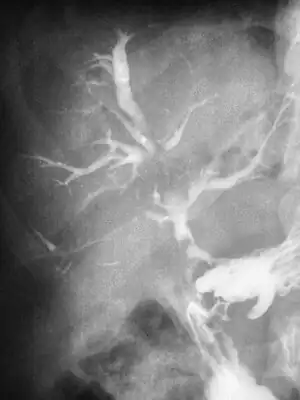

| Duodeno Biliary Fistula | |

For bronchobilary fistula, the following tests are performed: 1) ultrasound abdomen, may show subdiaphragmatic collection around the surface of the right lobe of the liver. 2) preoperative chest X-ray, may demonstrate mild to moderate right-sided pleural effusion without an active lung pathology. 3) CT scan, may reveal focal collection along the liver's right lateral margin, which can be communicating with one of the right lower lobe bronchi, supporting the diagnosis of a BBF.[1]